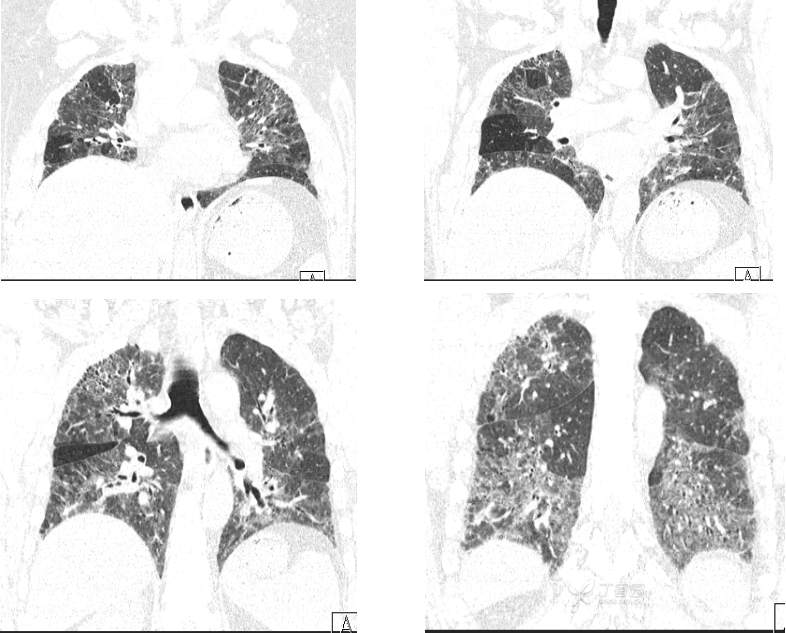

CT---肺窗---冠状位